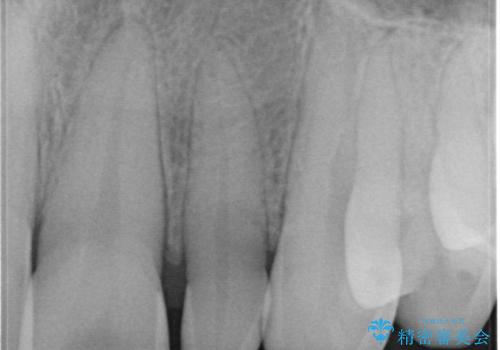

- 矯正治療で配列した矮小歯をオールセラミッククラウンで修復治療を行いました。

オールセラミッククラウンは、隣の歯に合わせて色調を調整することができるため非常に綺麗に仕上がります。